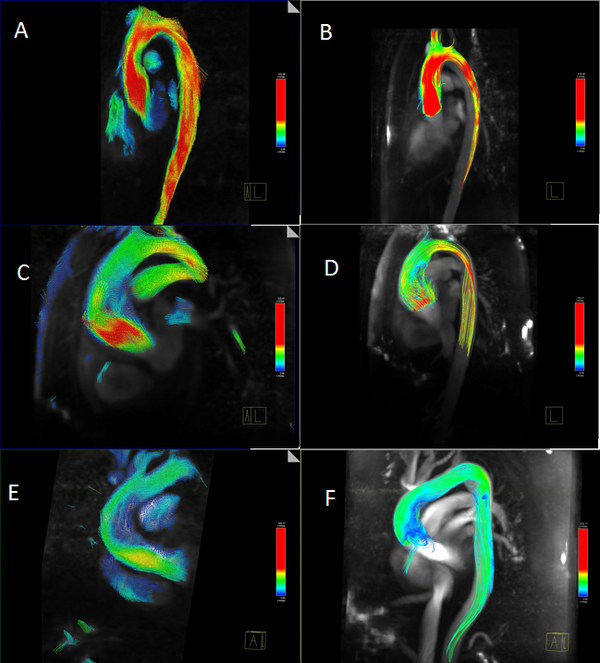

Other importance feature in many cardiovascular diseases is the helical flow patterns and turbulent blood flow, characterized by fast random temporal and spatial velocities fluctuations[25]. These irregular and rapid fluctuations are not present in healthy situations, and play also a key role in some cardiovascular pathologies. The helical flow patterns show a measure(index) of blood flow complexity, and therefore, is an important factor in the development of cardiovascular disease, as shown in figure 4. Given the fluid flow velocity vector field u, the vorticity vector field w is the curl of the velocity field:

It is a theorem of inviscid fluid mechanics that the helicity of a vortex tube is preserved over time. However, if a vortex tube is stretched, then its cross sectional area decreases, and the magnitude of the vorticity w increases, lowering the pressure at the center of the vortex. So, from a blood flow dynamics, the stretching of longitudinal vortex tubes could be a indicators of a cardiovascular pathology [26]. These effects are directly correlated with the oscillatory shear index [6].

|

| Figure 4: Left: Streamlines in a healthy aorta. Right: Streamlines in unhealthy aorta |

It is thought that the initial dilatation is caused partly by degeneration of the medial elastin and smooth muscles in the arterial wall or by the effect of the wall shear stress. Vessel wall remodeling as a result of shear stress alteration is accompanied by synthesis and secretion of NO, growth factors and metalloproteins, which contribute to aneurysm pathogenesis. Genetics and risk factors like smoking, hypertension, chronic obstructive pulmonary disease(COPD), inflammation and atherosclerosis play key roles in aneurysms genesis and progression[49]. In this context, there are few predictors of the aorta dilatation available in the clinical practice. Mainly, they are based on the aortic diameter and increasing aortic size. Currently, the accepted values have been changing over time and they are actually being discussed by the groups with experience, for example, [50][51] in TAA patients or [52][53] in AAA patients. There is also a hemodynamic factor of parietal stress in the aortic dilatation, which is currently a little-known factor. Prior works, related TAA, have confirmed the presence of different flux in bicuspid aortic valve without aortic dilation compared to tricuspid aortic valves patterns by using cardiac magnetic resonance imaging (cardiac MRI). Abnormal flow patterns have been also detected in aneurysms located in the ascending aorta which confirms flow jets to the anterolateral wall of the aorta [54]. It is also known that shear stresses play an important role in the initiation, progression and rupture of aneurysms[55][56]. Vorticity inside the aneurysm is connected to aneurysm plaque or thrombus formation [5][11]. Figure 7 shows some DI's in an Aortic Abdominal Aneurysm(AAA)[15].

1.2.1.4 Aortic Coarctation

Aortic coarctation(CoA) occurs approximately in 10% of patients with congenital heart defects and represents a narrowing of the descending aorta (see paper 1). Due to the reduction in the aorta descending diameter, high pressure gradients can appear across the CoA, resulting in an increased cardiac workload in the left ventricle during systole [57]. The narrowing of the aorta creates a flow jet with high velocity, inducing a very complex turbulent flow field. Recently, researchers has characterized changes of hemodynamic parameters such as pulse blood pressure, aortic capacitance, and wall shear stress due to the presence of an aortic coarctation [57][58][59]. Hemodynamic changes caused by the coarctation can result in endothelial dysfunction [60], provoking non normal values of TAWSS or elevated OSI for CoA patients.